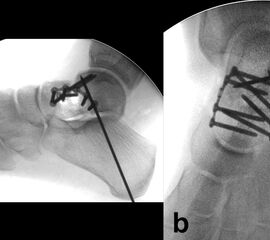

Die Reposition des Talushalses erfolgt unter wechselseitiger Sicht von medial und lateral 24. Zur Manipulation können senkrecht zur Fraktur in die Hauptfragmente eingebrachte Kirschnerdrähte hilfreich sein 4. Nach temporärer Retention mit axial eingebrachten Kirschnerdrähten und visueller sowie Bildwandlerkontrolle werden zur Stabilisierung vorzugsweise Schrauben benutzt (Abb. 6). Müssen diese nahe zum Talonavicular-Gelenk eingebracht werden, sind Doppelgewindeschrauben oder die Verwendung einer Kopfraumfräse zum Versenken des Schraubenkopfes unter Knorpelniveau erforderlich. In jedem Fall sollte bei der Schraubenosteosynthese aufgrund der typischerweise vorliegenden medialen Trümmerzonen auf die Vermeidung von Zugkräften geachtet werden, um eine Verkürzung der medialen Seite des Talus mit nachfolgender Varusfehlstellung zu vermeiden 30. Kleinste, nicht refixierbare Fragmente werden verworfen, um freien Gelenkkörpern vorzubeugen. Auf der lateralen Seite hingegen liegt recht häufig eine einfache Fraktur vor, welche in einem Kortikalis-Sporn am Proc. fibularis tali ausläuft und sich für eine Zugschraubenosteosynthese eignet. Die Verwendung kanülierter Schrauben kann im Einzelfall hilfreich sein. Es ist jedoch darauf zu achten, dass es nach dem Überbohren des Führungsdrahtes nicht zu einer erneuten Dislokation der Fragmente kommt 24.

Verbleibt nach der Versorgung aller knöchernen Verletzungen eine ligamentäre Instabilität, so ist zur sicheren Bandheilung und damit auch Protektion der Osteosynthese eine temporäre Gelenktransfixierung für 6 Wochen indiziert 5. Dies betrifft nach der Versorgung von Talushals- und –korpusfrakturen eher das Subtalar-Gelenk (Abb. 10), nach Taluskopffrakturen eher das Chopart-Gelenk 12.

Das Behandlungskonzept sollte prinzipiell so konzipiert und umsetzbar sein, dass bei einer übungsstabilen Osteosynthese eine frühfunktionelle Behandlung begonnen werden kann. Eine Ausnahme stellen hochgradig instabile Frakturen oder Luxationsfrakturen dar, welche zusätzlich zur Osteosynthese eine temporäre Gelenktransfixierung benötigen 5. Diese erfolgt, falls erforderlich, mit Kirschnerdrähten für 6 Wochen, um eine stabile Bandheilung und eine erste Konsolidierung der Fraktur zu gewährleisten (s. Abb. 10).